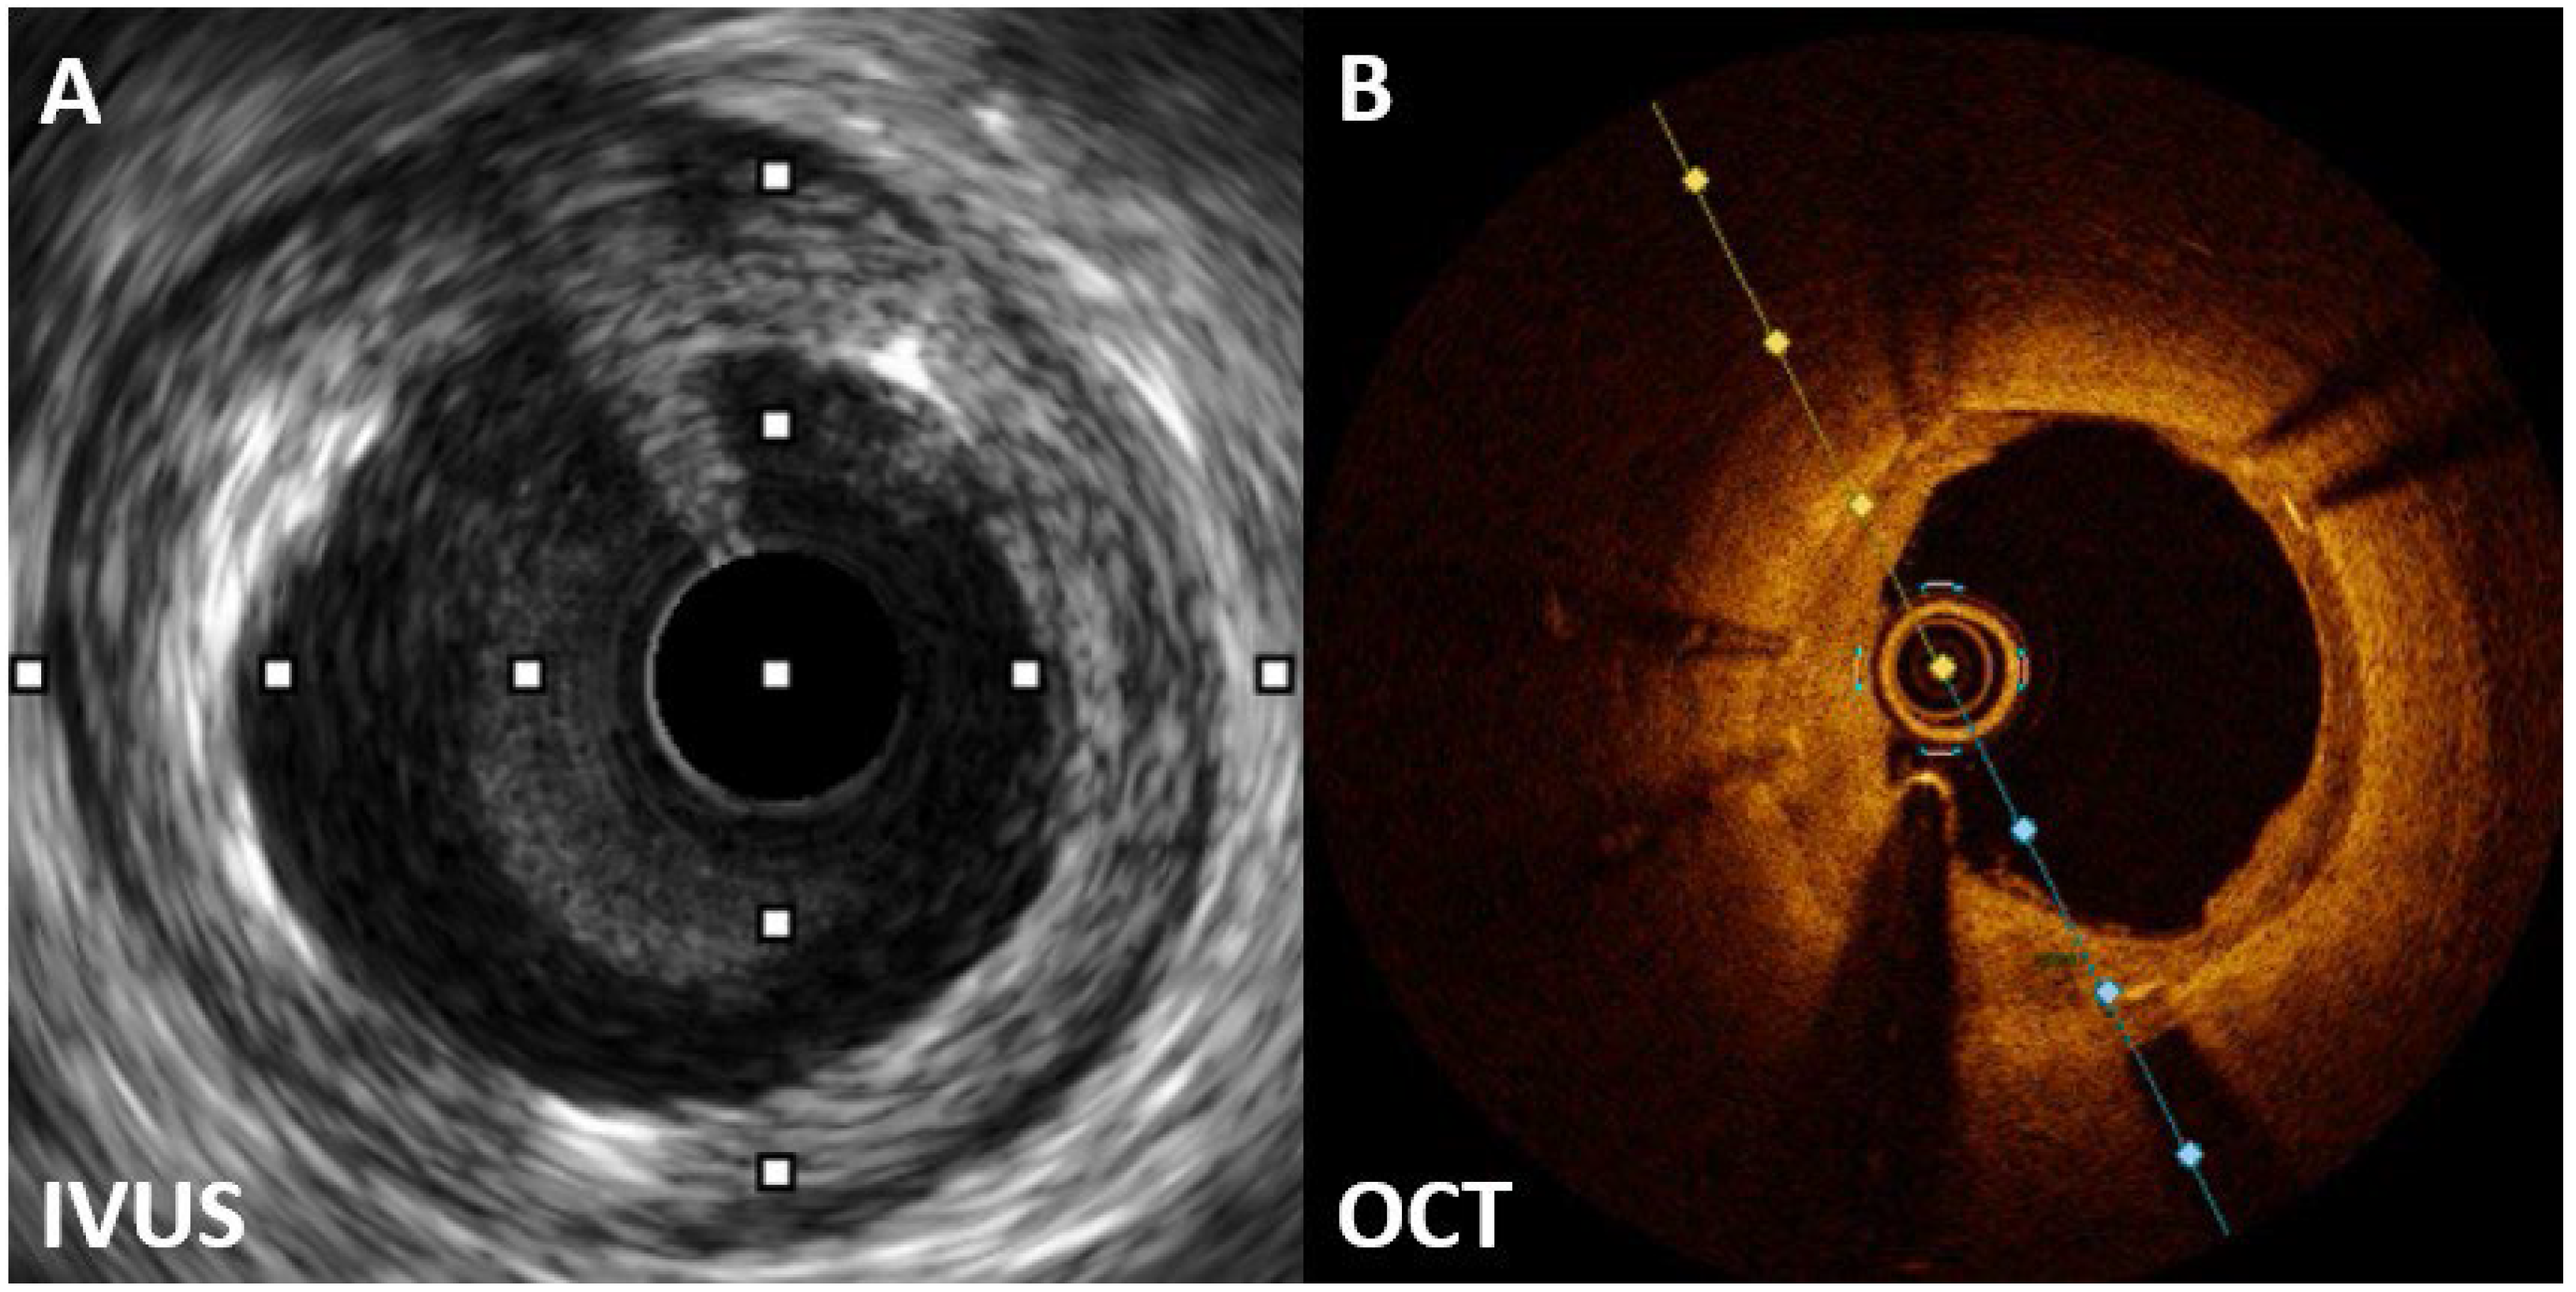

Coronary angiography on April 27, 2023, revealed severe ISR of the proximal LAD (Figure 1). A 60-MHz high-definition IVUS was performed, which revealed a homogenous echolucent appearance at an ISR of the SES (Figure 2A) and a suspected BH phenomenon.

Given the significant constriction of the lumen area of the ISR lesion, obtaining a high-quality OCT image without balloon predilatation is challenging. Hence, we chose the 2.0-mm balloon to minimize the effect on the original lesion. OCT revealed a layered pattern with a superficial high-signal intensity band adjacent to the luminal surface and a signal-poor region near the stent (Figure 2B). According to the above imaging findings, the patient was diagnosed with BH phenomenon through OCT.

Although the BH phenomenon is unusual in DES restenosis, establishing a universal mechanism is challenging. Tissue analysis of the BH revealed a primarily hypocellular matrix with areas rich in proteoglycans, possibly due to delayed vascular wound healing following SES implantation. The echolucent appearance is likely attributed to this hypocellular matrix and its high water content [9,10].

OCT revealed a layered structure with an inner layer with high-signal intensity and outer layers with low signal intensity. The low OCT signal intensity is a result of restenotic tissue rich in proteoglycan and poor in collagen matrix or fibrin-rich thrombus formation. Although various restenotic tissues can exhibit low OCT signal intensity, the consistent border and structure in this case suggest that the BH phenomenon in OCT may be due to the lack of organized mature connective tissue elements in the restenotic tissue [11,12].

Figure 2. A Homogenous echolucent appearance at an ISR of the sirolimus eluting stent. B The layered pattern with superficial high-signal intensity band adjacent to the luminal surface, and signal-poor region near the stent.